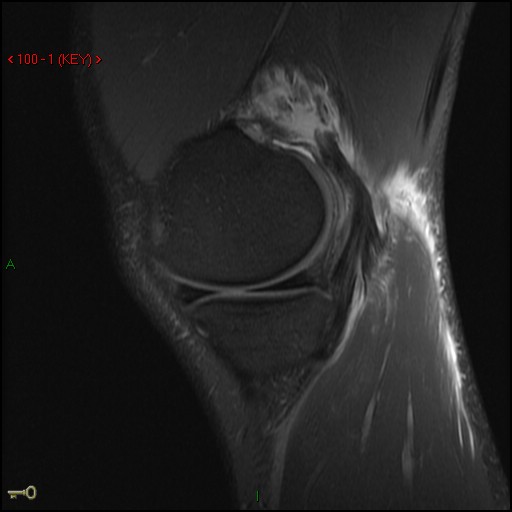

Figure 1 for case Medial head of gastrocnemius muscle ( RID2921 ) avulsion

Figure 1